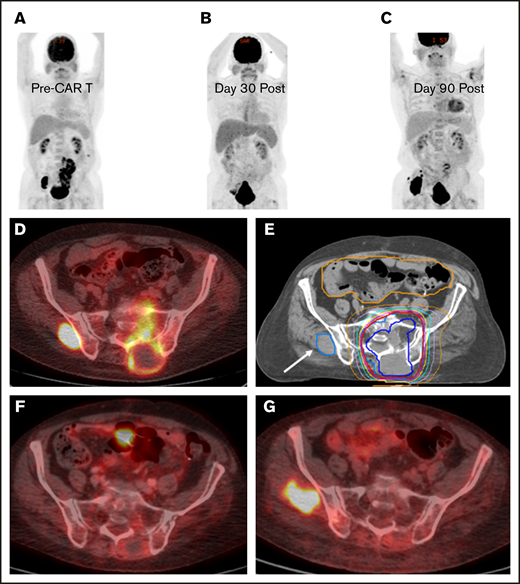

BT with a focal RT field in a CAR T-cell patient. Scout (A) and axial (D) images of a PET-CT scan in a male patient with primary refractory DLBCL who presented with cauda equina syndrome and a sacral mass. Emergent RT was administered with a 3-dimensional conformal RT plan that was transitioned to a volumetric-modulated arc therapy plan to a total dose of ∼43 Gy administered in 2.5-Gy fractions; the PET avid left gluteal mass (white arrow) was excluded from the RT field in an effort to limit bone marrow dose (E). The initial response assessment at day 30 revealed CR to therapy with a score of 2 on a 5-point scale (B,F). The 3-month post–axi-cel PET-CT scan revealed recurrent disease in the left gluteal region that was positive before axi-cel therapy but excluded from the RT field (C,G).